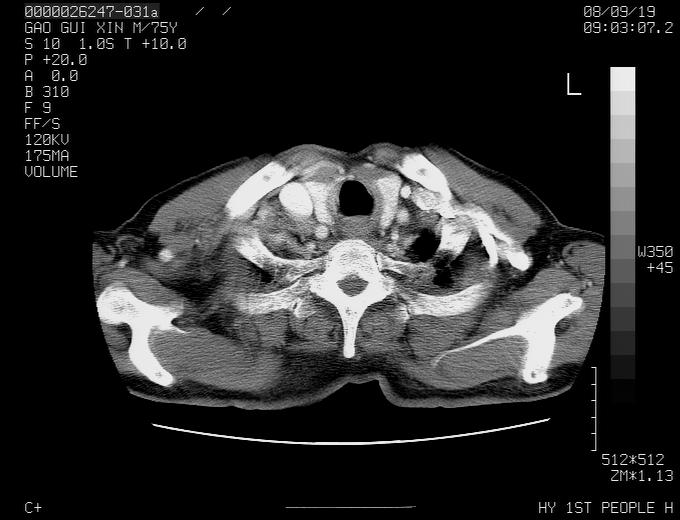

感谢各位老师的意见,左上肺病灶,我本人趋向结核,原因:左上肺见两个类圆形结节,仔细回顾4月份ct似乎原片在该处有条片状密度增高影,强化不明显。

现上传增强片,请各位老师仔细帮我看一下。

右上肺可见条索状影,并可见钙化,左上肺结节可以考虑为结核球,但气管前腔静脉后有肿大淋巴结,本人觉得左上肺结节不能排除转移瘤的可能,右上肺为陈旧性结核灶。

左肺上叶周围性肺癌并纵隔多组lnm.不可能是tb.

左肺上叶尖段瘢痕癌并纵隔淋巴结转移解释更好一些.

双上肺继发型肺结核,纵隔淋巴结结核可能性大,建议定期复查.

左肺周围癌并纵隔淋巴结转移,另一小结节是血管影

别再ct讨论了,一个纤支镜检查马上明确.肺癌不会错的!应该是低分化鳞癌.

左上肺周围型肺癌并纵隔淋巴结转移

1)左肺上叶尖段周围型肺癌并纵隔淋巴结转移。2)冠状动脉及主动脉钙化。

左上肺周围型肺癌并纵隔淋巴结转移。纤支镜检查